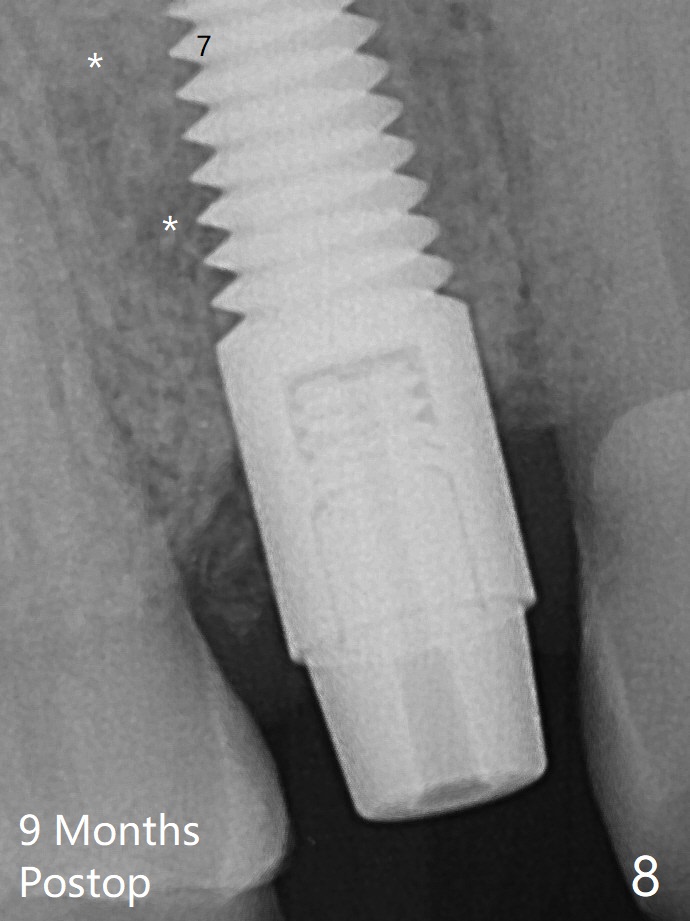

After extraction of the tooth #4 with fistula (Fig.1), the buccal bony defect is superior to the fistula. Before placement of a 4.5x17 mm tissue-level implant (Fig.2) and after osteotomy for bone-level one, PRF and mixture of autogenous bone and allograft are pushed from the socket through the buccal defect for repair (Fig.3 arrowheads). The trajectory of the implant (Fig.4) is consistent with design (Fig.5). The fistula reduces in size and in redness, while the apical elevation (as related to the underlying bone graft) remains prominent 13 days postop (Fig.6,7 *). The distal defect has been apparently repaired 9 months postop (Fig.8 *, as compared to immediately post bone graft in Fig.2). The distal defect has been apparently repaired 9 months postop (Fig.8 *, as compared to immediately post bone graft in Fig.2). The fistula disappears (Fig.9).